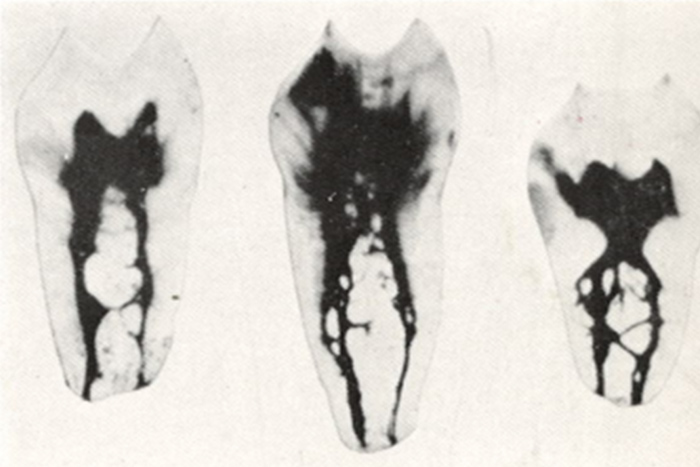

下の写真を見てください。この神経取れると思いますか。

本物の歯の神経の管を染めて、その走行を調べた写真です。複雑怪奇です。実際、この神経を全部きれいにとり切るのは不可能です。

患者さんは、神経を取るというと一本の糸をすーと引くと取れてくるようなイメージをお持ちのようです。私も歯科医になる前はそんなイメージを持っていましたが、神経を取る処置はまるで難攻不落の敵に立ち向かうほどの忍耐力を必要とします。大臼歯などは2時間ぐらいかかることもあります。